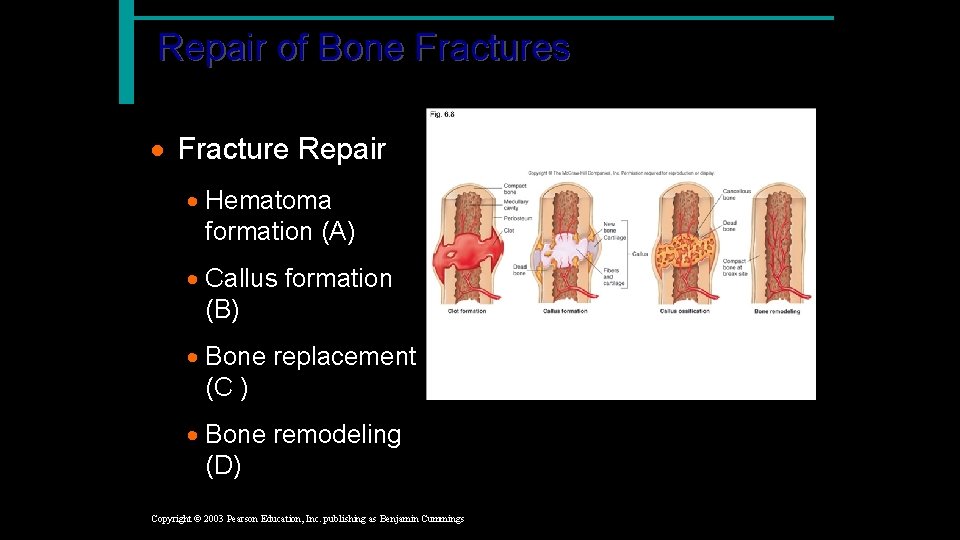

Repair of Bone Fractures · Hematoma (blood clot) is formed · Break is splinted by fibrocartilage · forms a callus (chondroblasts, other cells, and vessels) · Callus is replaced by a bone (osteoblasts) · Bony callus is remodeled (osteoclasts) Copyright © 2003 Pearson Education, Inc. publishing as Benjamin Cummings Slide 5. 18

Repair of Bone Fractures · Fracture Repair · Hematoma formation (A) · Callus formation (B) · Bone replacement (C ) A · Bone remodeling (D) Copyright © 2003 Pearson Education, Inc. publishing as Benjamin Cummings B C D